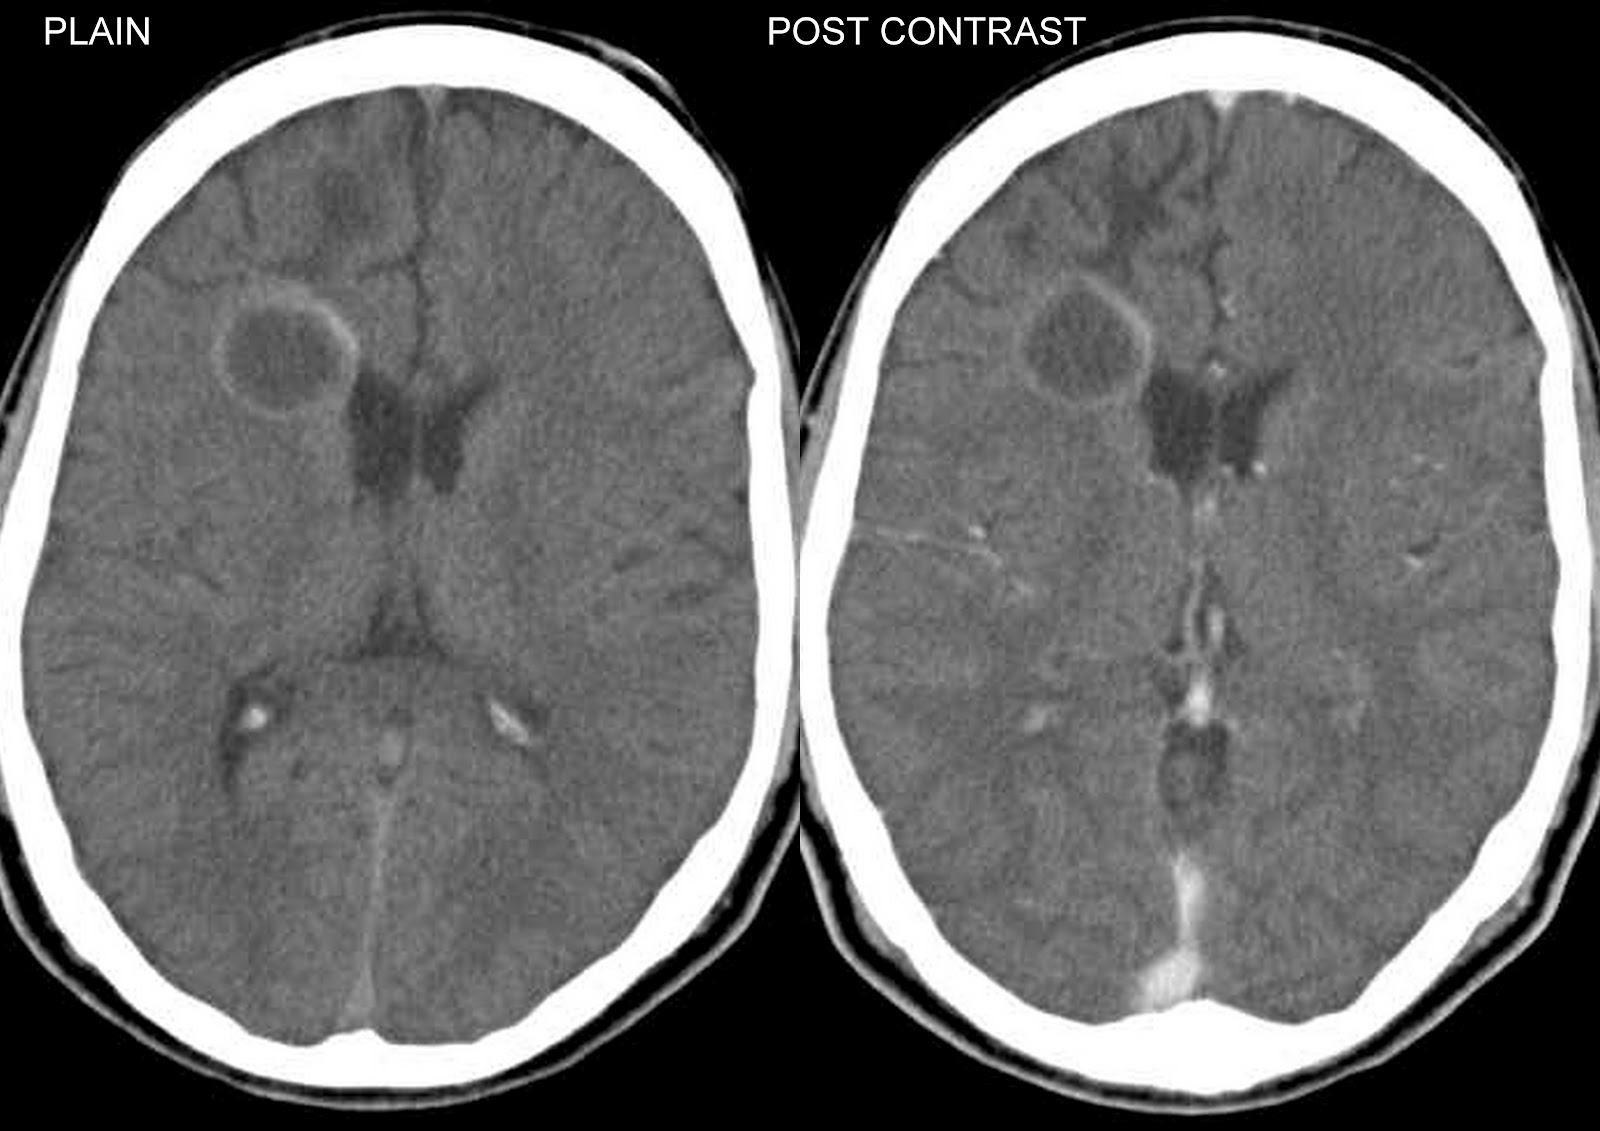

Мрт при инфекционных заболеваниях мозга - фото презентация